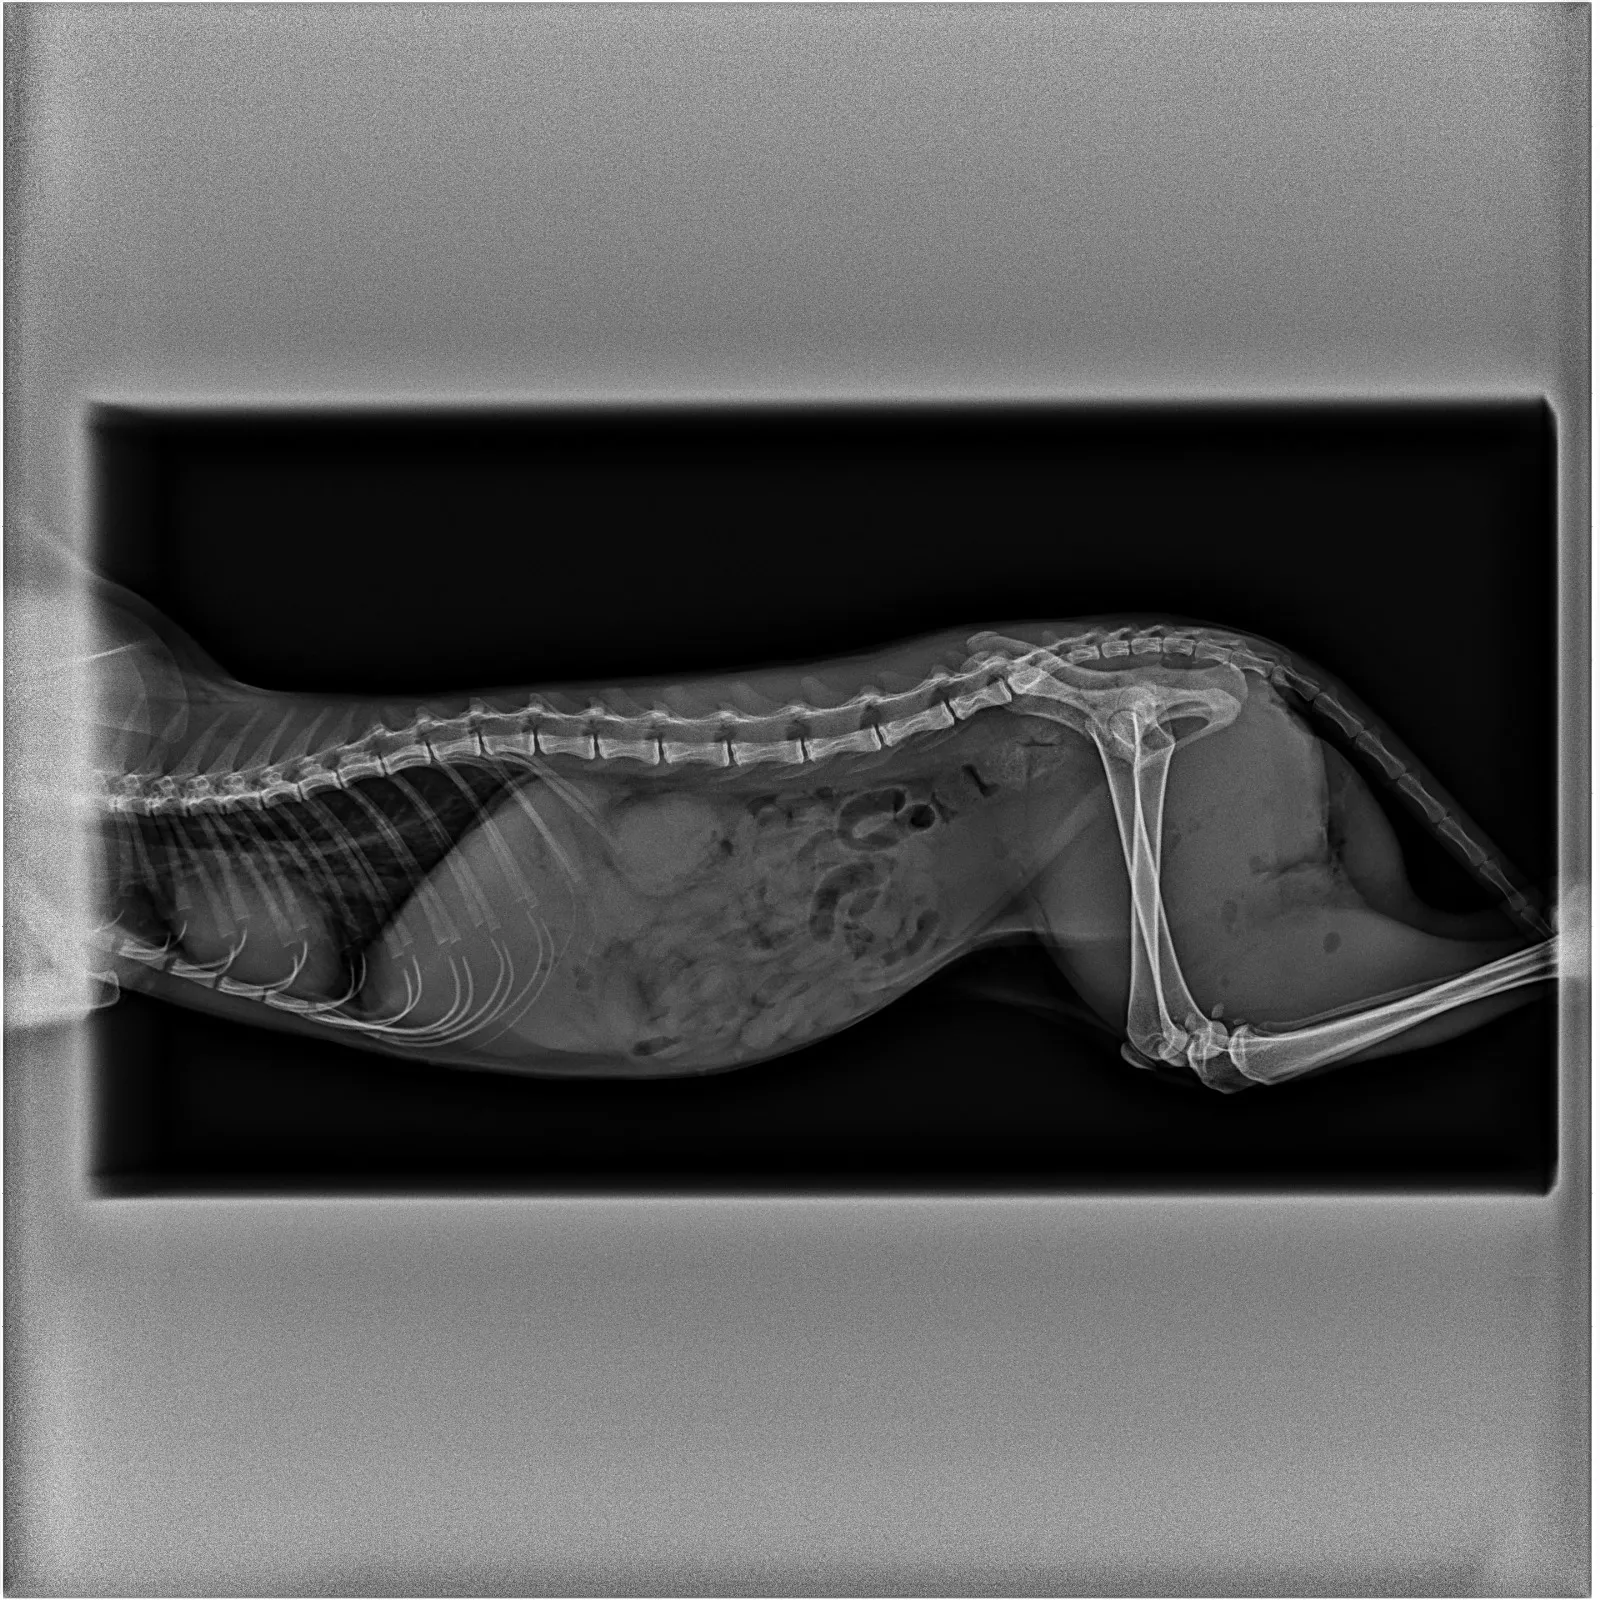

Ha sido encontrada con un cambio trascendental en su existencia: del carácter mimoso de antaño ha pasado a la desconfianza total. En la radiografía se aprecia que su cuerpo aloja dos perdigones, uno junto al ojo y otro en el omóplato de la patita izquierda. Tiene el fémur roto y, presumiblemente por una patada en la cara, un colmillo asoma fuera de la boca. Además, su anca trasera derecha revela un mordisco, muy probablemente de perro.